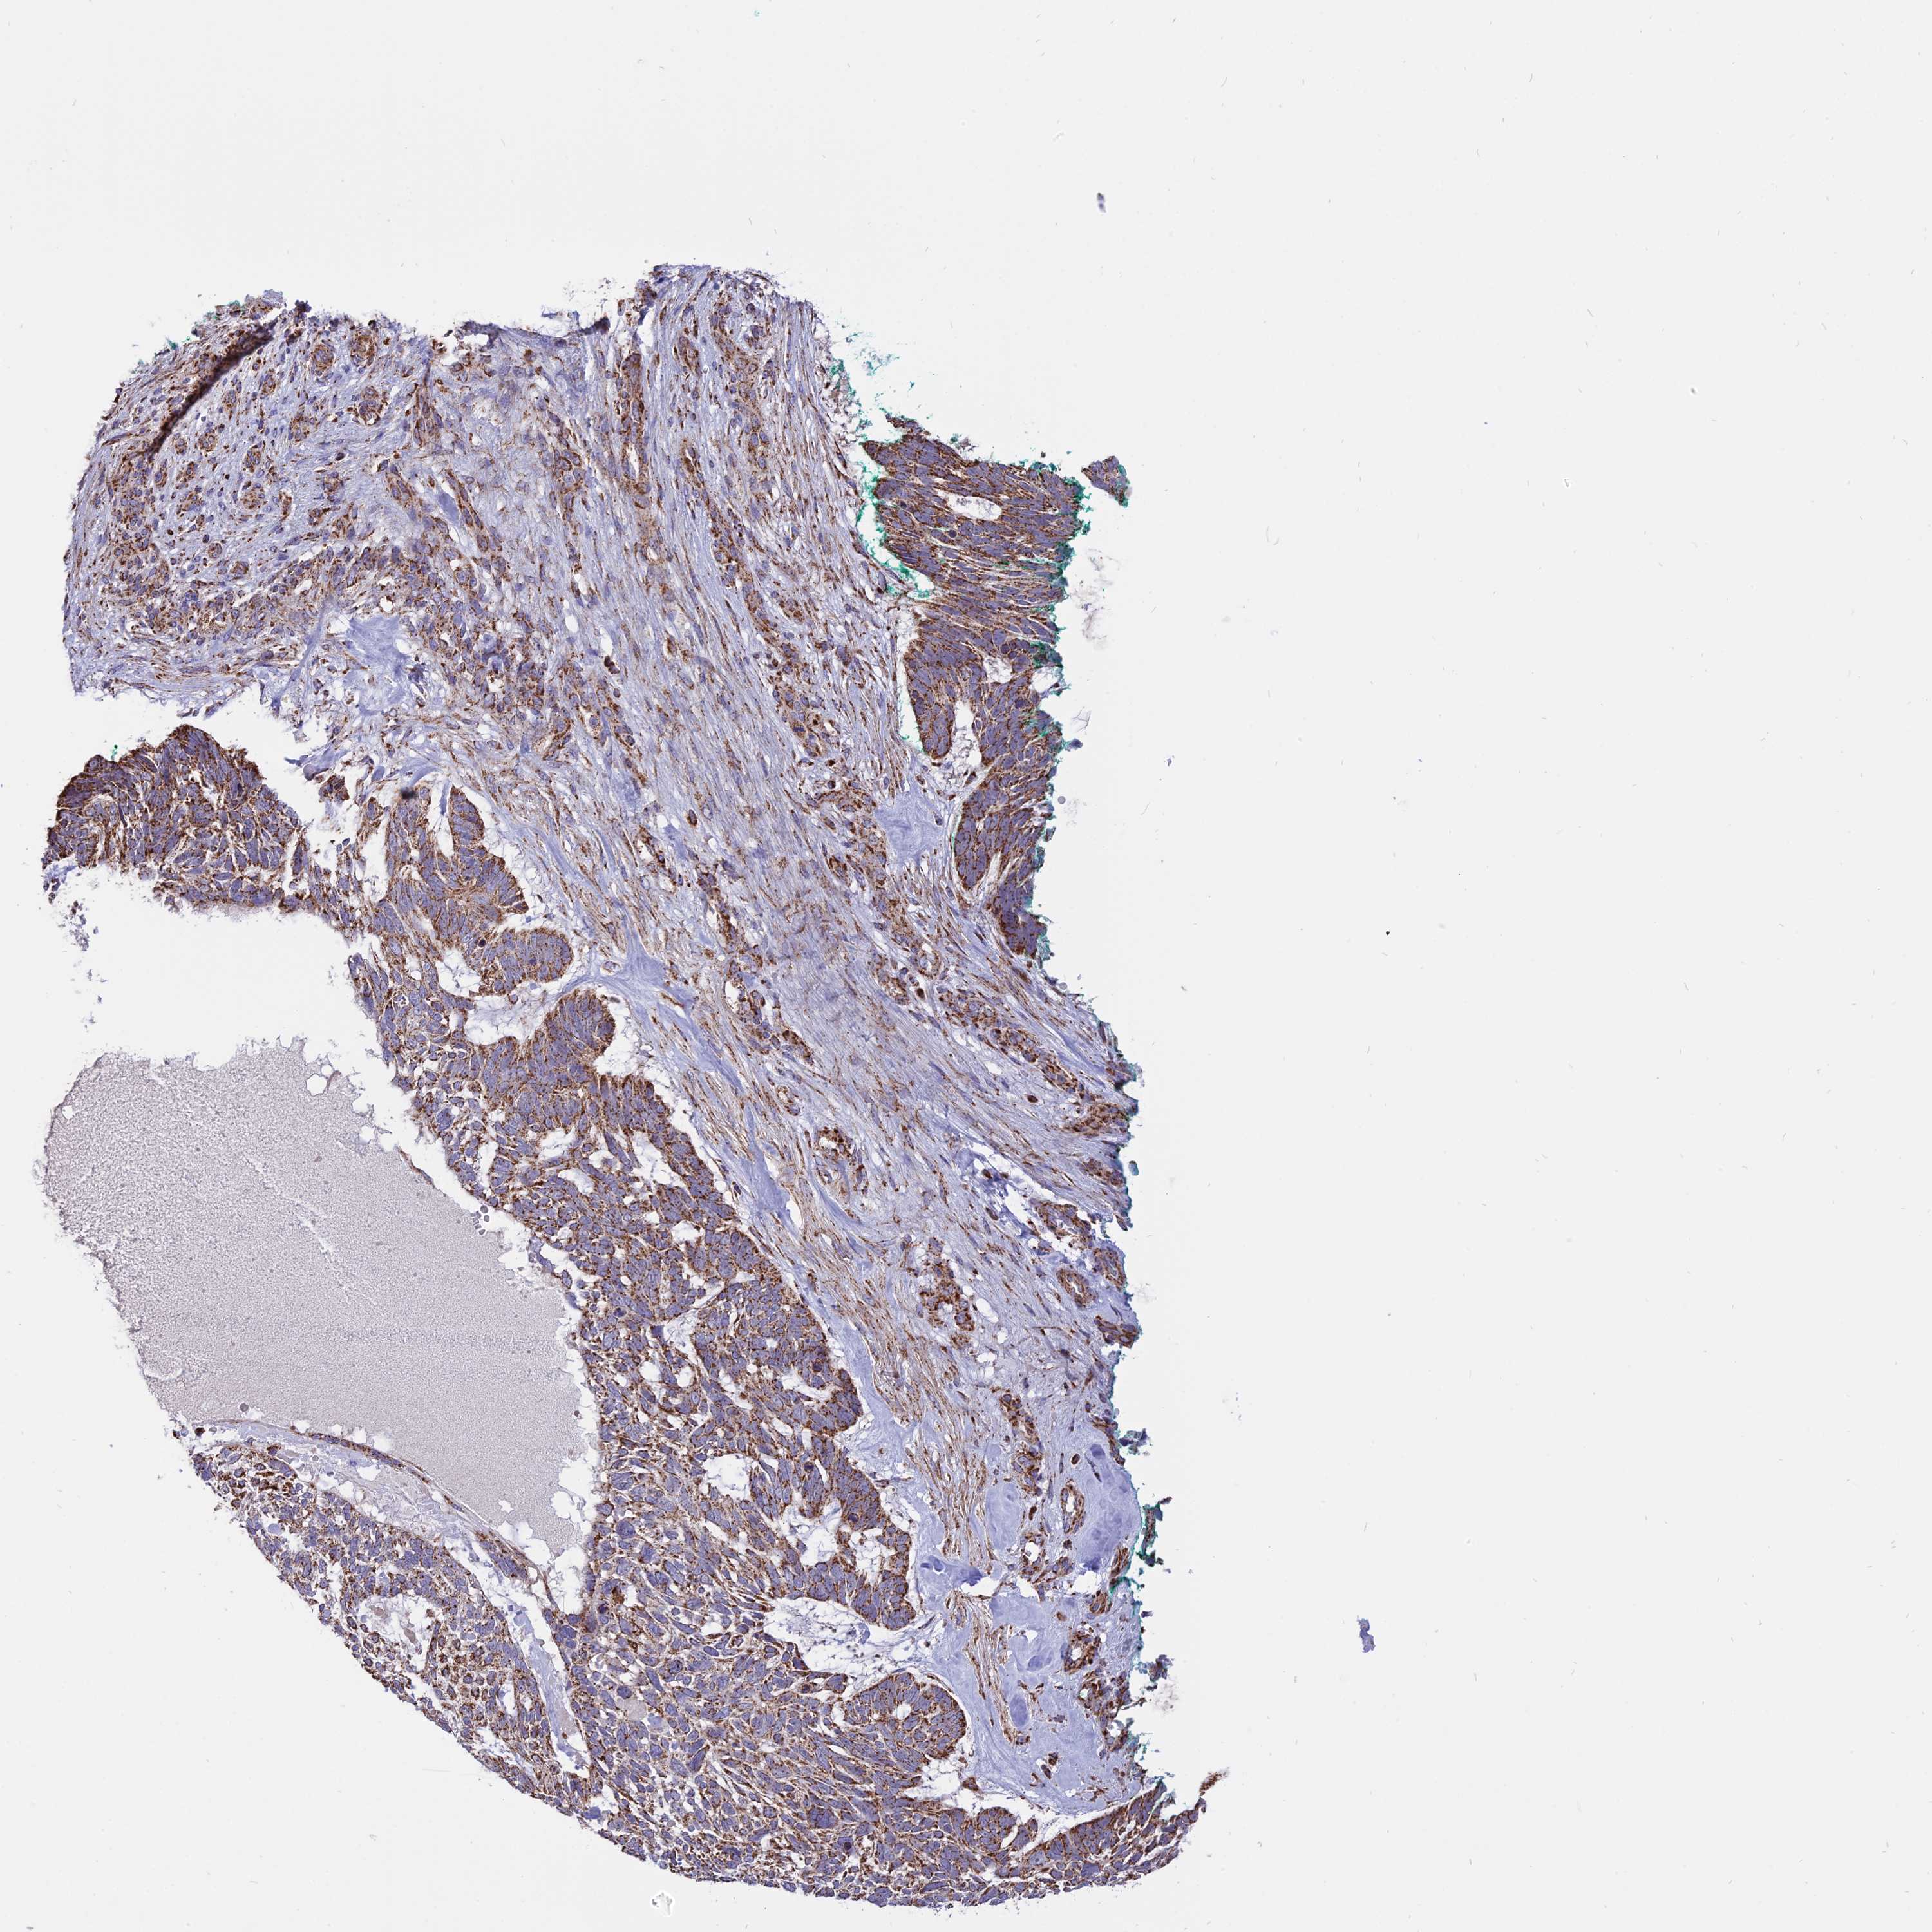

SKIN CANCER - Protein expressioni

A mouse-over function shows sample information and annotation data. Click on an image to view it in a full screen mode. Samples can be filtered based on level of antibody staining by selecting one or several of the following categories: high, medium, low and not detected. The assay and annotation is described here.

Each image is clickable and will lead to virtual microscopy that enables deeper exploration of all samples and also displays staining intensity scores, fraction scores and subcellular localization as well as patient and tissue information for each sample.

Antibody HPA042459

Squamous cell carcinoma, metastatic, NOS